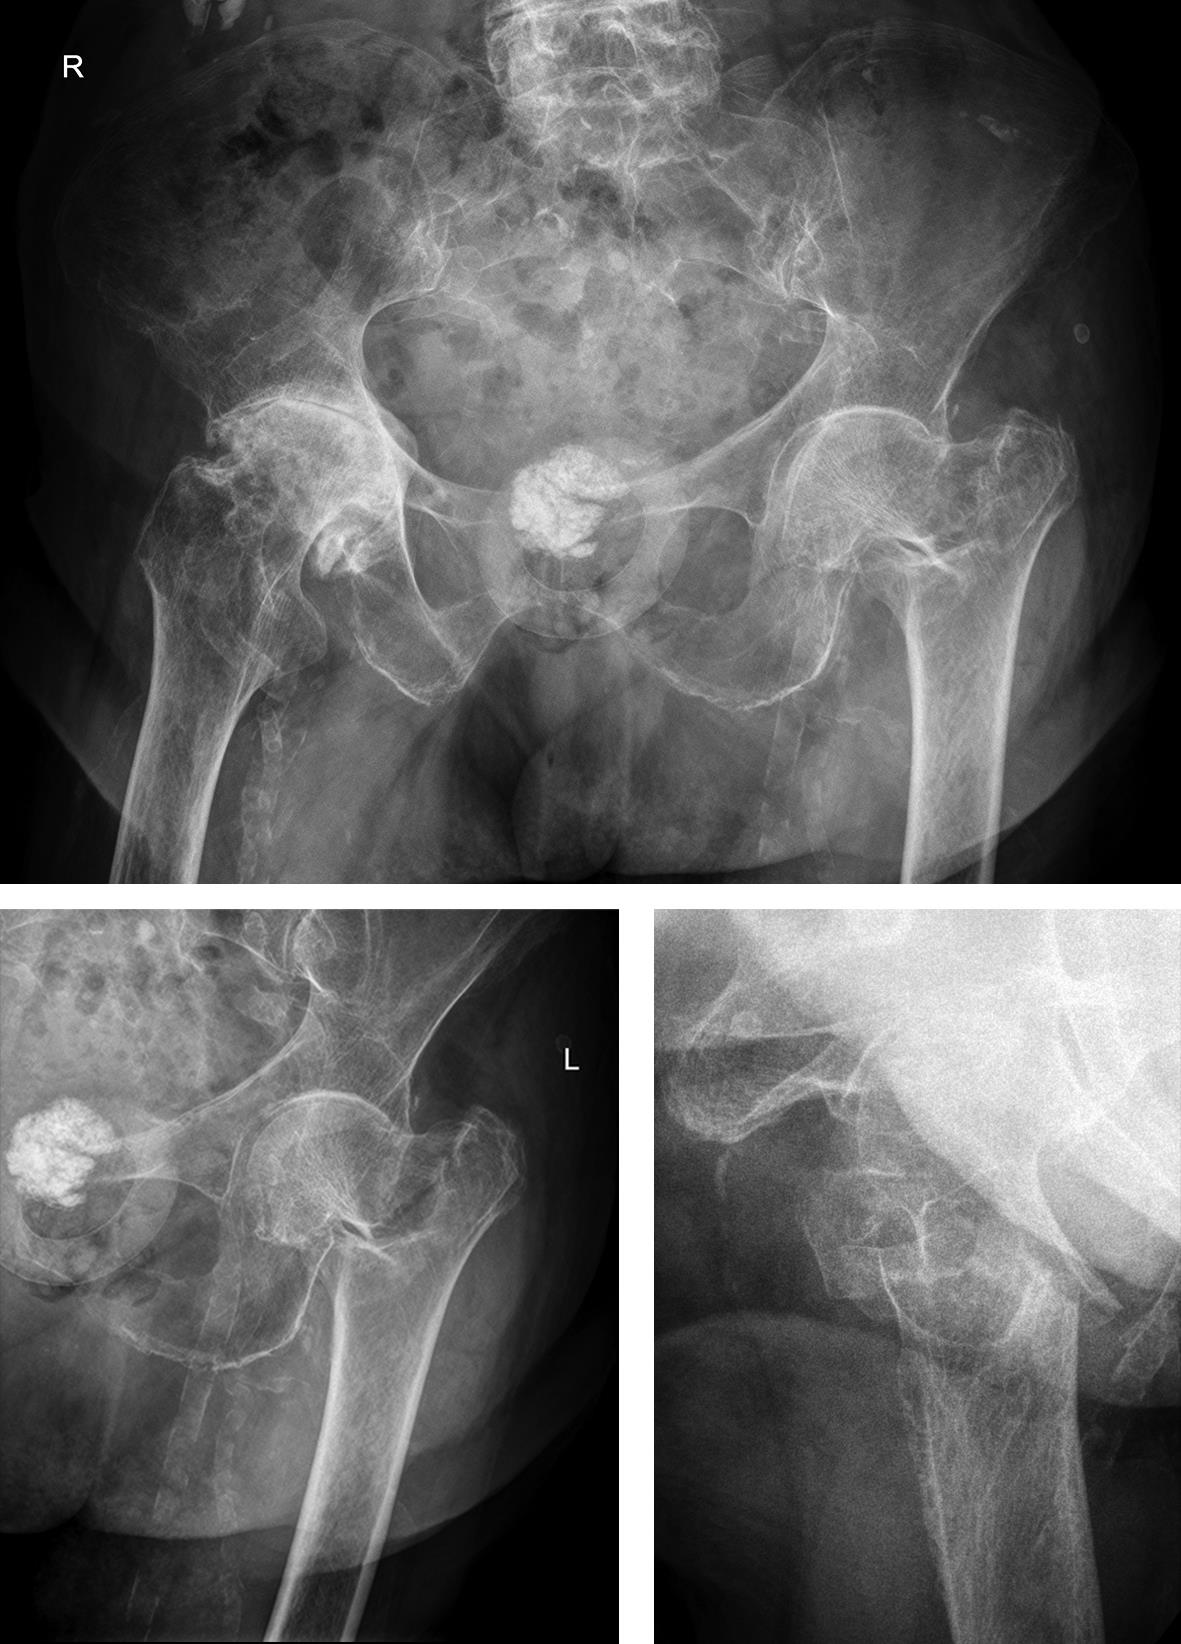

Case 2: Pertrochanteric fracture

A 98-year-old female patient sustained a pertrochanteric fracture of the left proximal femur due to fall in her nursing home (Fig 1). There was significant pain and coxarthritis in the right hip, and hypertension. Surgery was performed within 24 hours. There was an indication for augmentation due to the instability of the fracture. The patient additionally suffered from osteoporosis and dementia.

Case provided by Hiroaki Minehara, Sagamihara, Japan